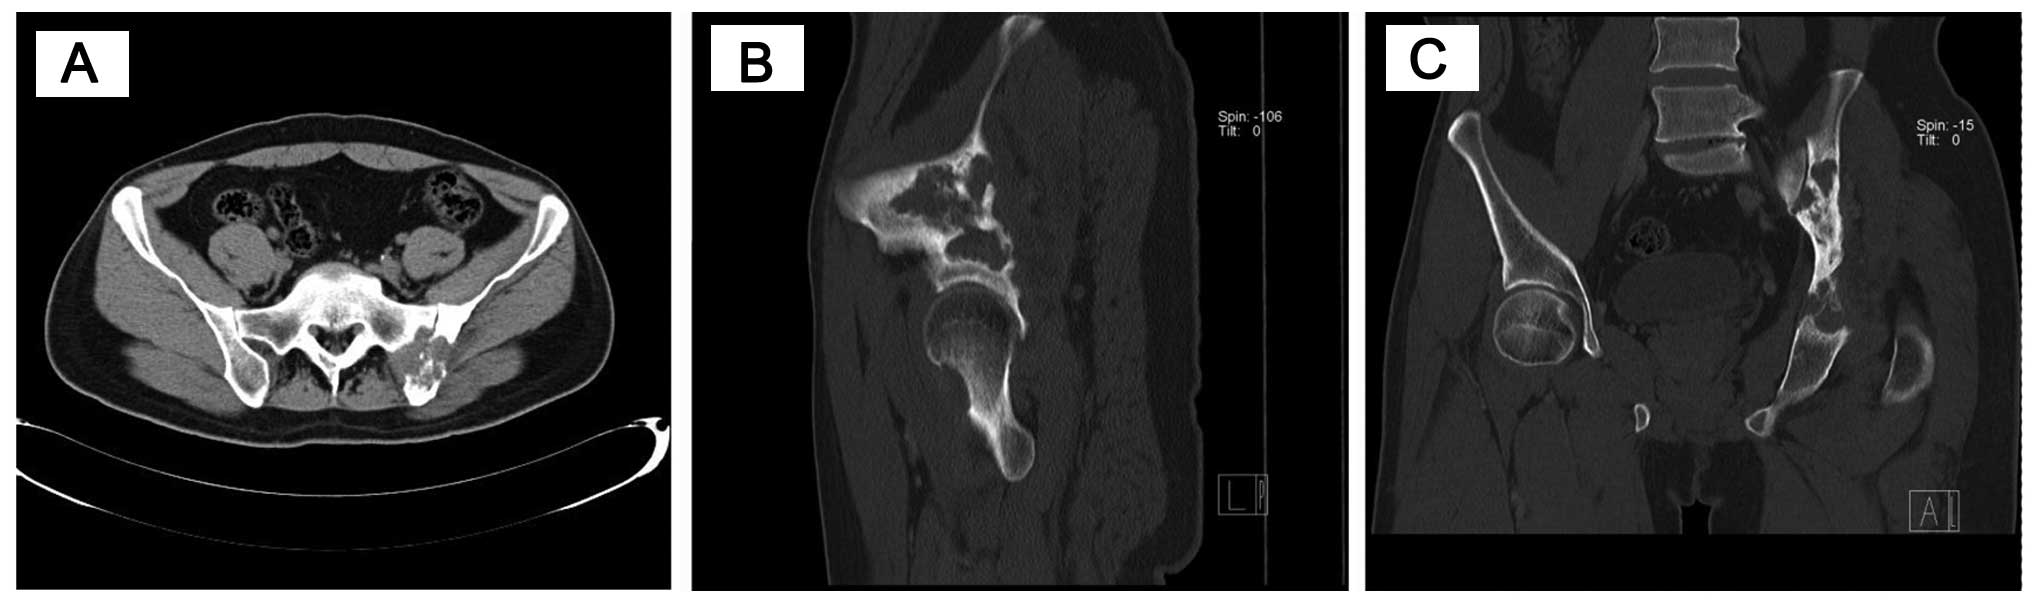

The images obtained by a multidetector computed tomography (CT) device were reconstructed in a variety of planes and interpreted in soft tissue, bone or lung windows. Pulmonary and pelvic diagnostic CT examination revealed the distribution of the disease: The corpus of the sacroiliac joint, sacrum, acetabulum and femoral head were occupied by a destructive soft tissue mass (Fig. 1).

Figure 1.

(A) Computed tomography multiplanar reconstruction images showing an osteolytic lesion around the left sacroiliac joint with surrounding edematous soft tissues. (B) Coronal and (C) sagittal plane multiplanar reconstruction of the pelvis showing a bone lesion on the left, with reactive sclerosis.